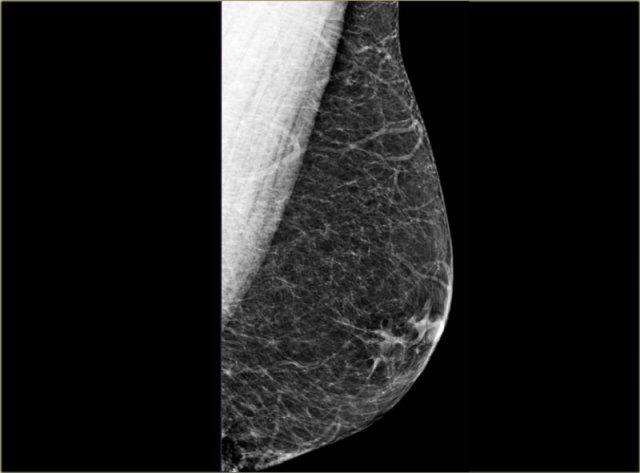

Các hình ảnh bên trái trông đơn giản như những vú nữ nhỏ.

Đây là bệnh nhân đang điều trị bằng liệu pháp estrogen cho ung thư tuyến tiền liệt.